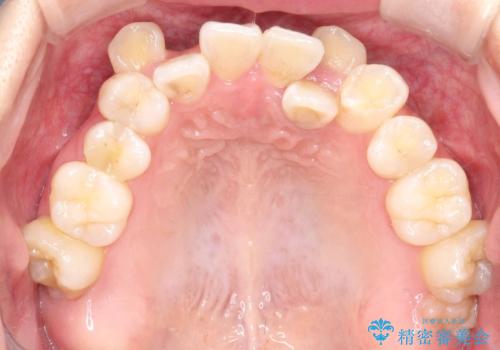

かなり綺麗に並ぶ事ができ大変満足していただけました。

叢生量がかなり多かったのですが、歯肉退縮も失活歯も無くとても綺麗な歯並びになりました。

歯のでこぼこは、歯周病や虫歯のリスクも、とても高いので、見た目のみならず、将来の歯の寿命自体もかなり伸ばす事が出来た治療でした。

歯の寿命を伸ばす為には、歯磨きをし易い環境を作る事がとても大切です。